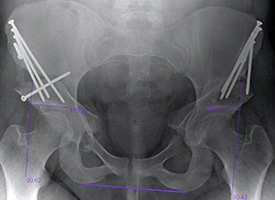

POST OP

This x-ray demonstrates bilateral periacetabular osteotomies to increase coverage and stability of the hip joint. Notice that the roof of the hip socket is now horizontal, and the ball of the hip joint is now fully covered. This can decrease pain and preserve the hip joint.